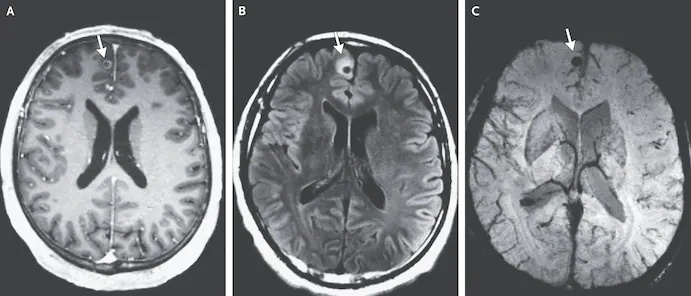

Hình chụp CT của nam bệnh nhân tại Mỹ cho thấy sán dây tồn tại trong não người này suốt 20 năm, song, nó đã chết và bị vôi hóa. Ảnh: New England Journal of Medicine/AP.

Tại đây, các bác sĩ kiểm tra xét nghiệm máu và các chỉ số khác đều không phát hiện bất thường. Chỉ khi có hình chụp CT não, ê-kíp điều trị mới phát hiện 3 vết tổn thương trong não và vật thể lạ.

Các bác sĩ chẩn đoán anh ta mắc bệnh neurocysticercosis (nhiễm ấu trùng sán lợn). Đây là thuật ngữ thường được dùng để chỉ các u nang trong nhu mô não. Bệnh nhân có triệu chứng co giật, hiếm gặp hơn là đau đầu.

Andrew J. Cole, Bệnh viện Đa khoa Massachusetts, tác giả chính của nghiên cứu, cho biết trước khi lên cơn co giật, người đàn ông 38 tuổi hoàn toàn khỏe mạnh và không có gì bất thường. Điều khiến nhóm tác giả chú ý đó là sán dây trong não của bệnh nhân đã chết từ lâu nhưng vẫn gây ra các cơn động kinh.

Edward T. Ryan, Giám đốc khoa Bệnh truyền nhiễm toàn cầu, Bệnh viện Đa khoa Massachusetts, đồng tác giả, trả lời phỏng vấn của tờ The Washington Post: “Trường hợp này khá đặc biệt. Ấu trùng sán dây đã chết và bị vôi hóa trong 1-2 thập kỷ. Thực tế, tình trạng nhiễm sán dây của người đàn ông đã khỏi từ lâu, nhưng một phần mô não bị sẹo và trở thành nguyên nhân gây co giật”.